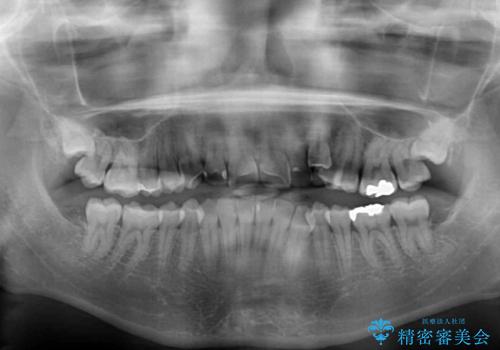

- 顕著な八重歯など、上下前歯のデコボコとスペースを気にして来院された患者様です。

八重歯改善には第一小臼歯の抜歯が必要であり、移動量が多いことから補助装置により八重歯を引き込むこととしました。

インビザラインでの治療をご希望であったので、インビザラインにて行うこととしましたが、右側前歯の改善にはワイヤー矯正が必要となる可能性があることをお伝えした上で治療を開始しました。

補助装置だけでなく、部分的にワイヤー矯正も使用しましたが、上下のスペースは改善しきれず、側切歯(前から2番目の歯)や顕著な八重歯は、インビザラインで治療するには限界があることがよく分かりました。